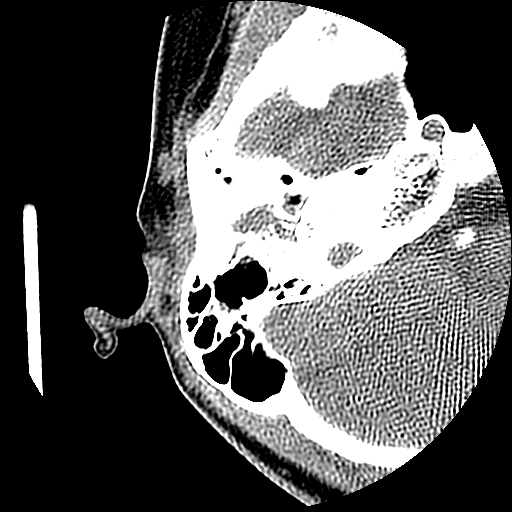

以下是引用随光逐影在2009-8-19 7:25:00的发言:[br]右侧慢性中耳乳突炎,右侧中耳腔及外耳道肉芽肿或胆脂瘤形成。